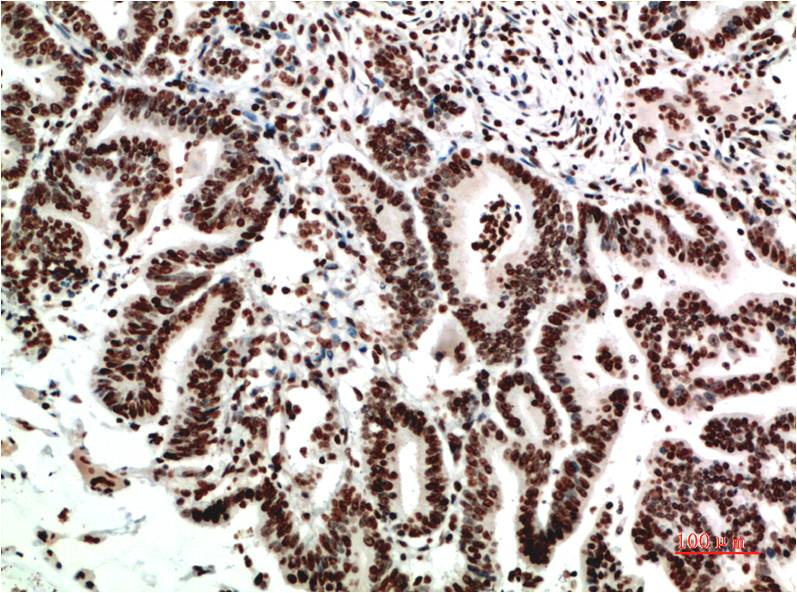

COX-2 Mouse Monoclonal Antibody(2G1)

Catalog NO.:BE3661

Applications :IHC

Reactivity :H,R,M

Recommended dilutions: IHC 1:100-200

Specificity: The COX-2 Mouse Monoclonal Antibody can detects endogenous COX-2 proteins.